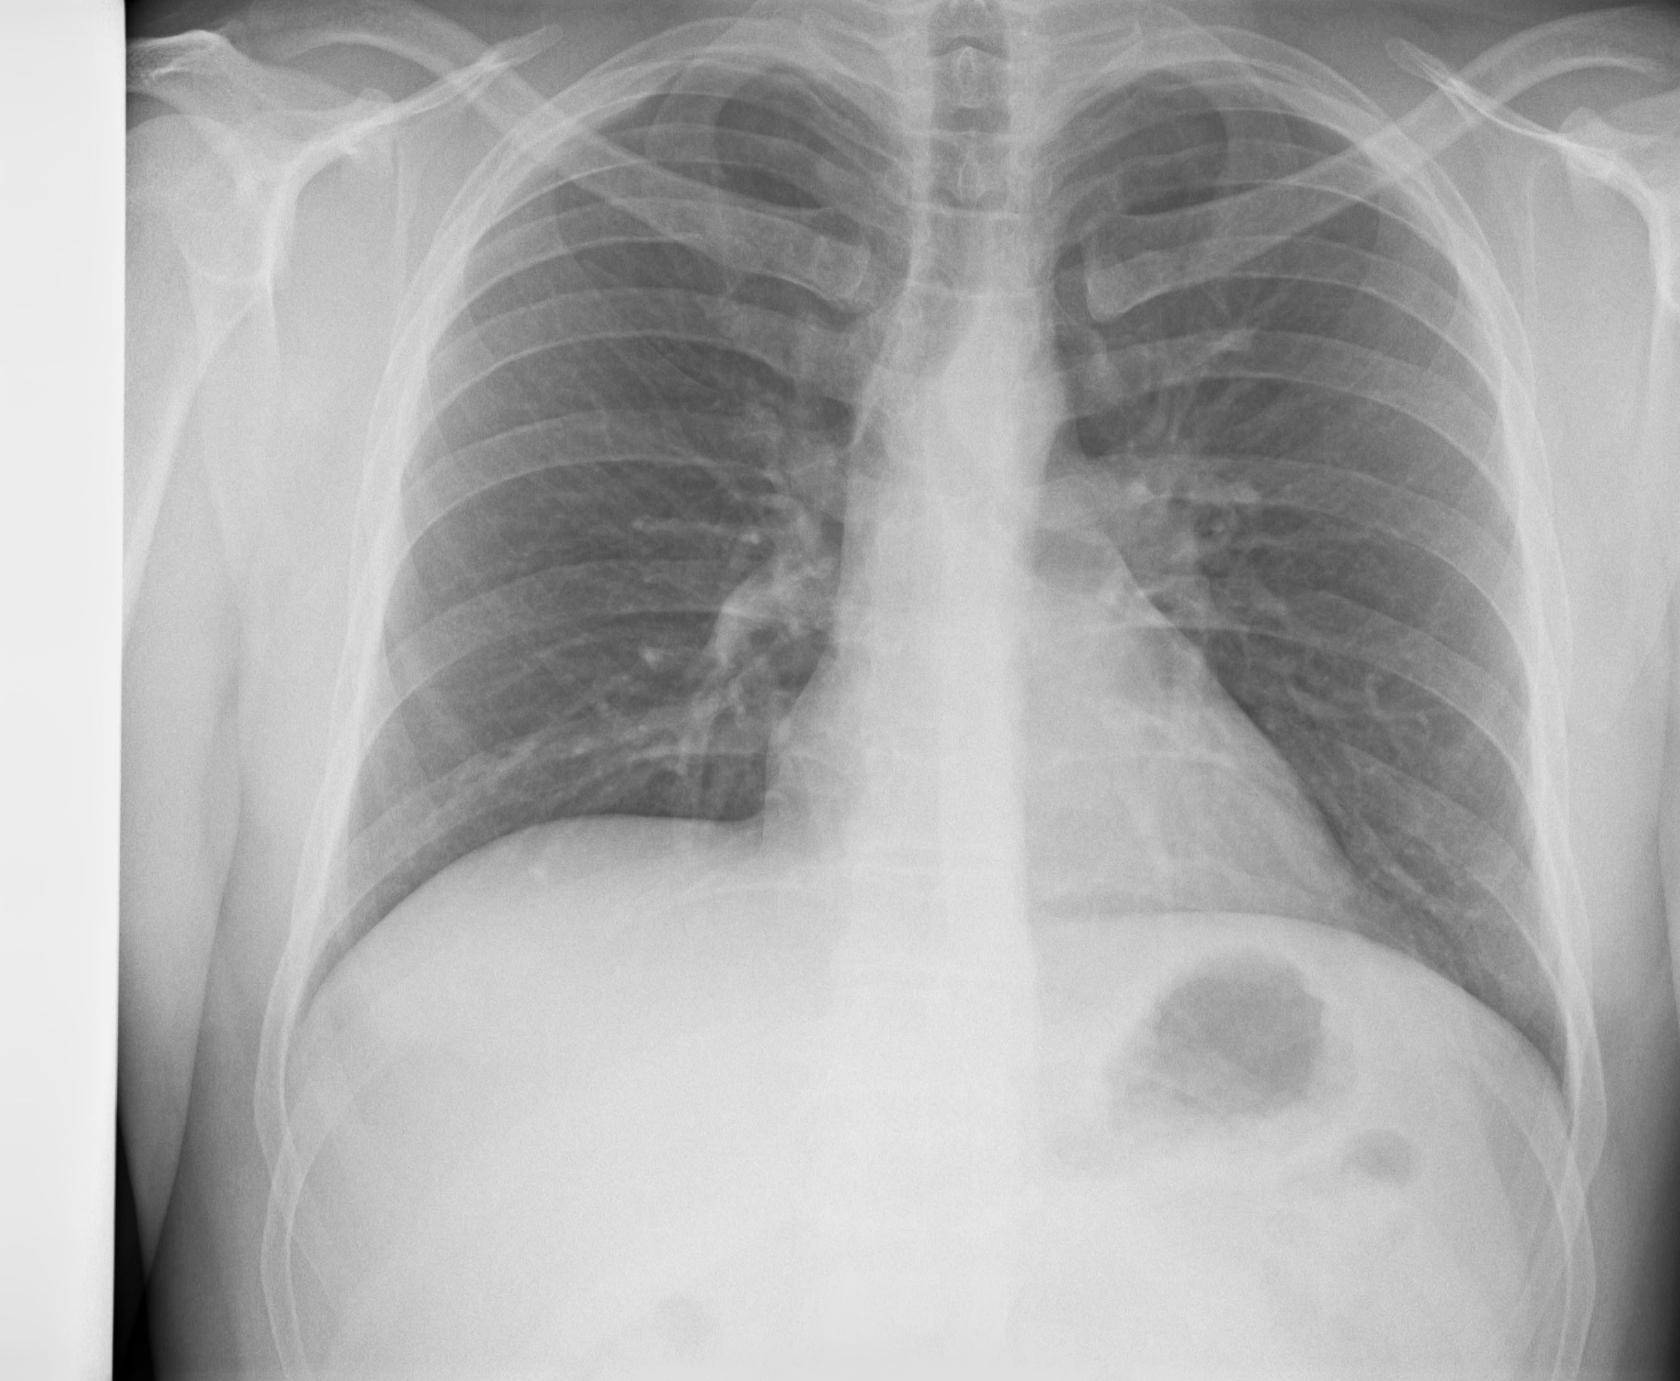

Рентген здоровых легких: примеры снимков и советы

Раздел: Сокровищница опыта